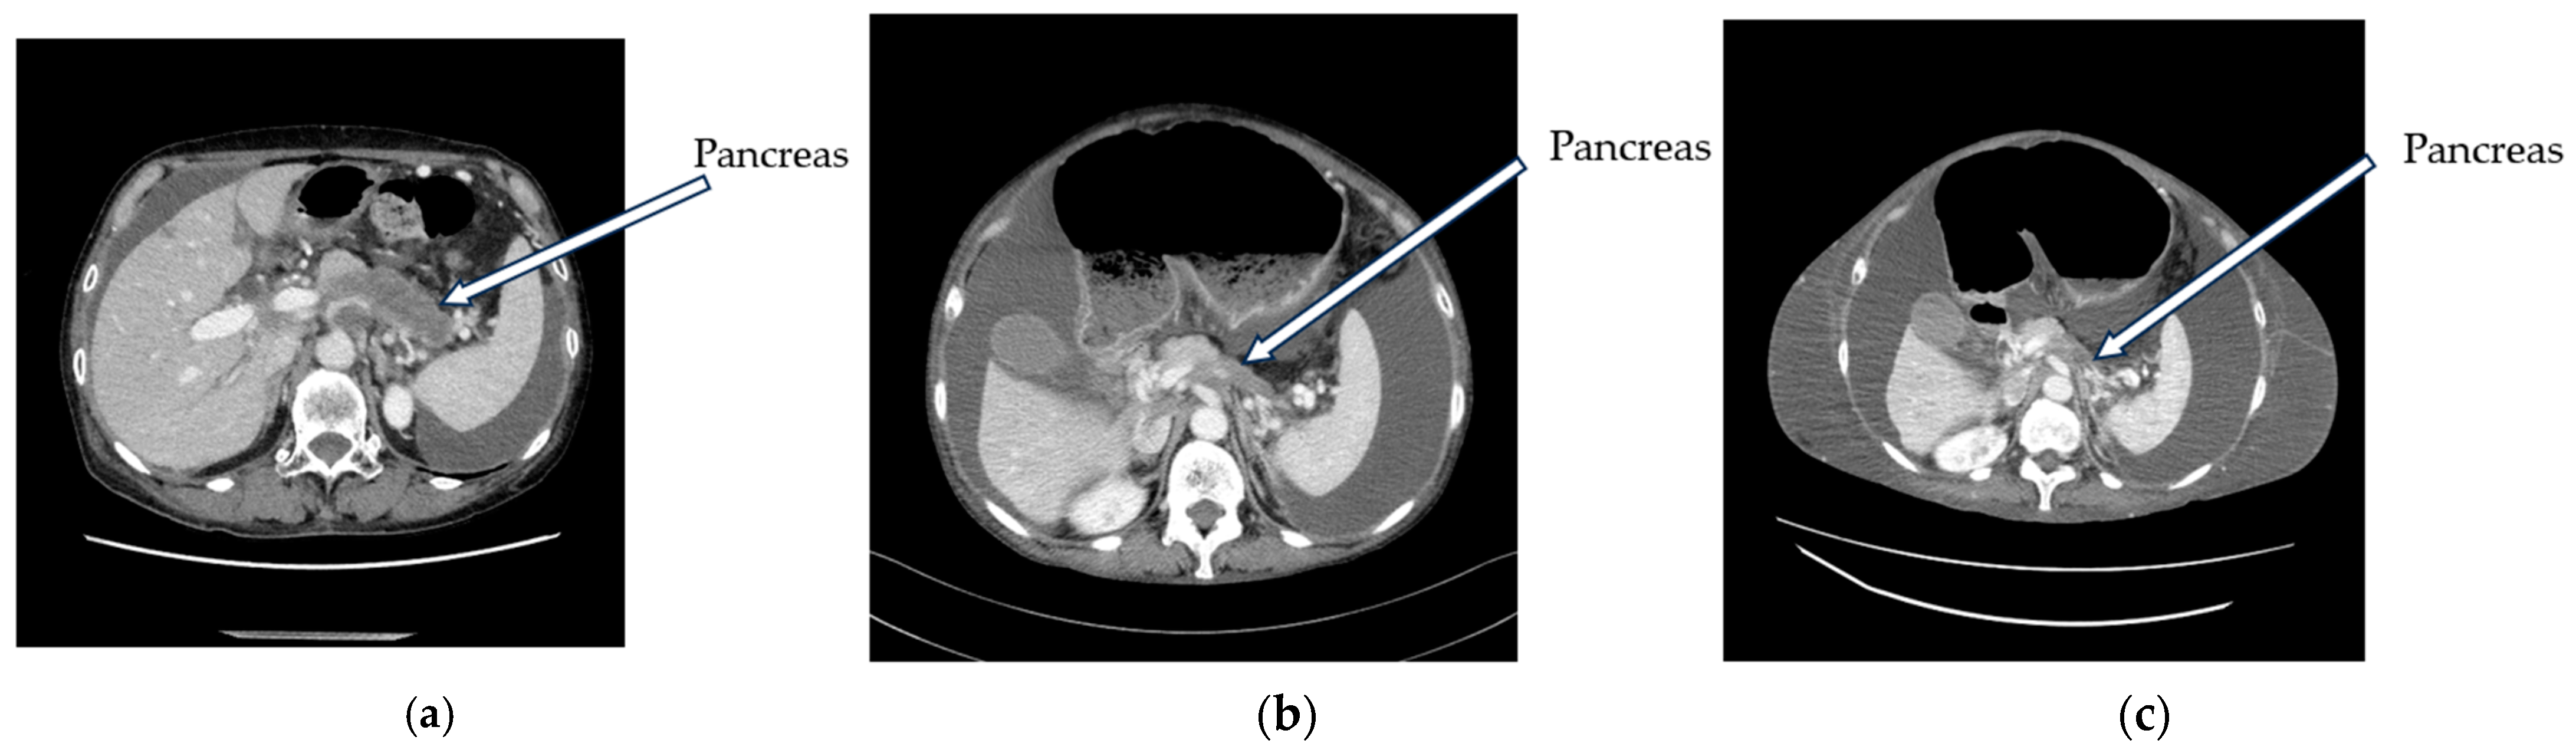

2. Case Presentation